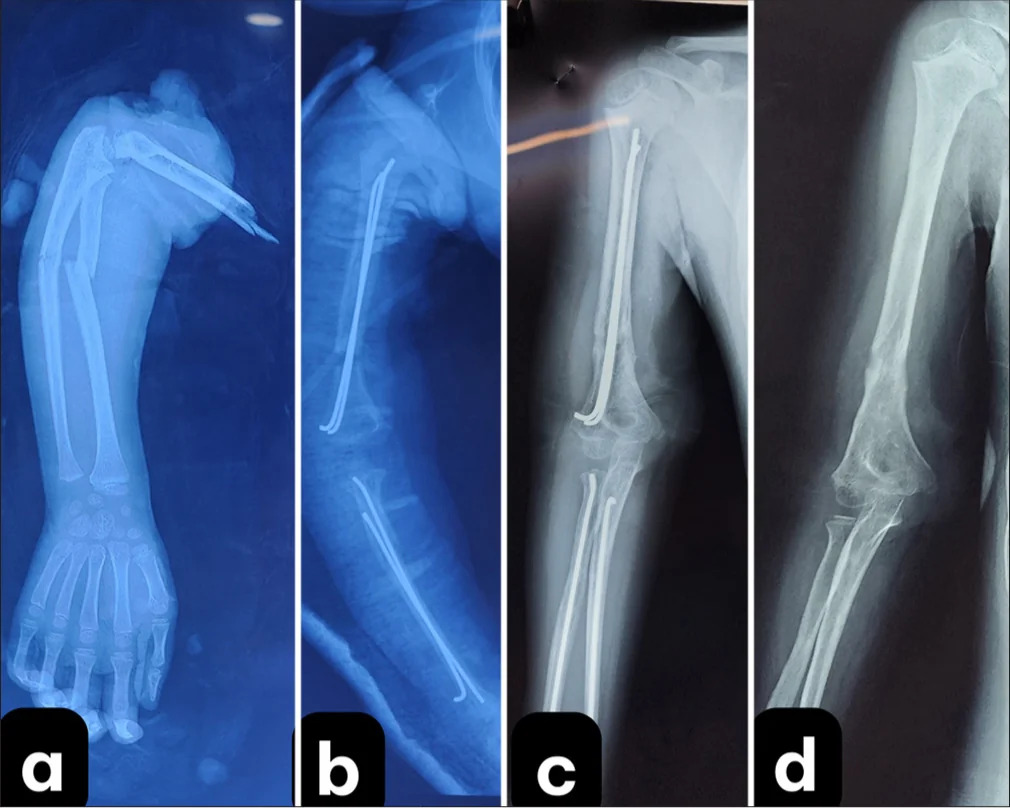

Fig 2: X-ray images before and after surgery.

Fig 4: (a) forearm bone fixation with intramedullary nailing, 1: forearm positioned on the C-arm machine for manipulation; and (b) harvesting the great saphenous vein for graft

The patient was supported by the family in daily muscle strengthening exercises. We instructed the family to perform passive range-of-motion exercises for the baby’s shoulder, elbow, and hand, including simple exercises to assist with shoulder abduction and adduction, elbow flexion and extension, wrist flexion and extension, and finger movement. These exercises were to be repeated multiple times a day, with no limitation on the number of repetitions, with monthly radiographs to monitor bone healing during the first 3 months. Bone healing was confirmed to be complete, and all fixation devices were removed in the 8th month. Starting from the 3rd month post-surgery, the patient could flex and extend the elbow, and electromyography (EMG) showed recovery of the radial nerve. By the 4th month, wrist extension was possible. At the 12th month, the patient was able to flex the fingers, but thumb opposition had not yet been achieved [Video 1]. EMG at the 10th month indicated recovery of the median and ulnar nerves.